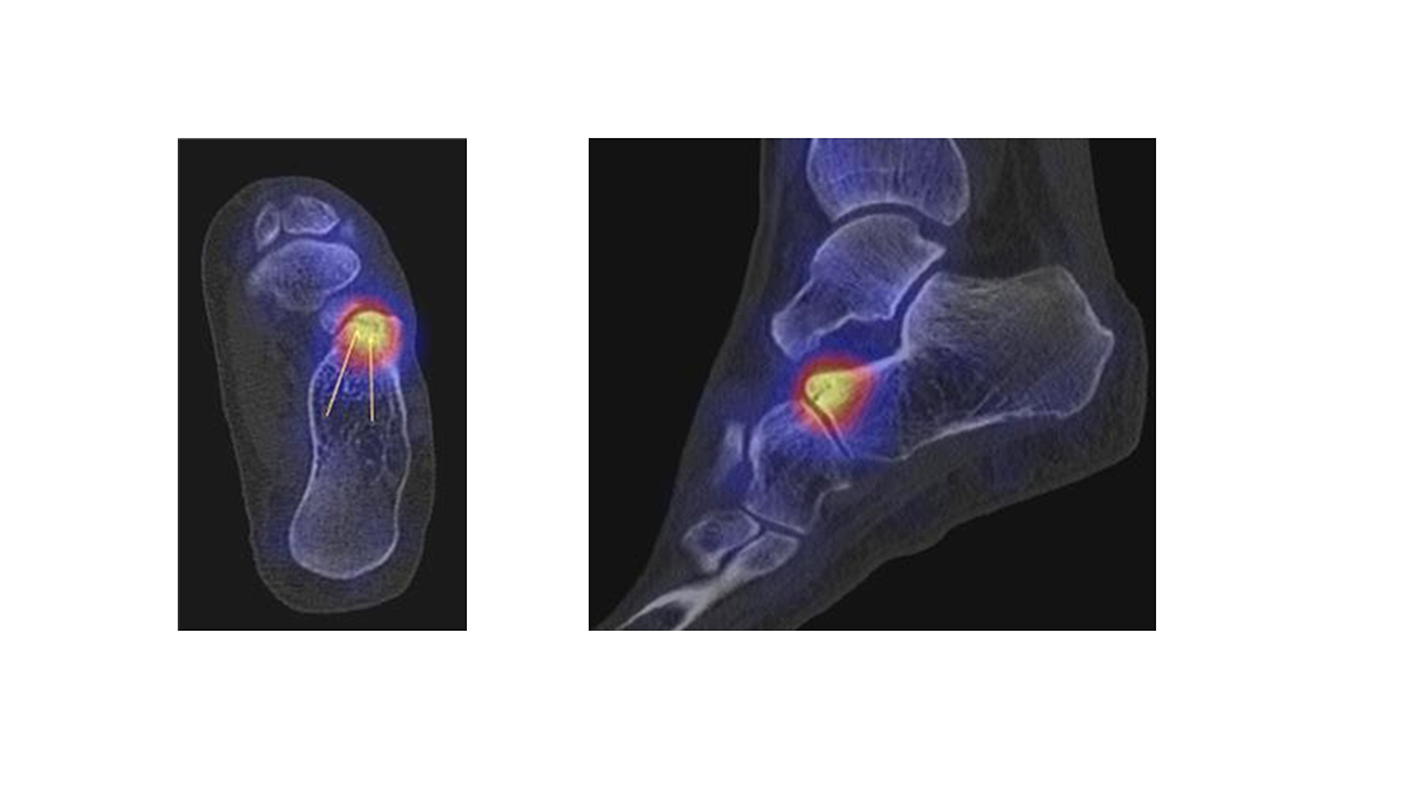

Abbildung 2.1.

Bildbeispiele symptomatische OCL

Zum Lesen der Bildbeschreibung und zur Vollansicht bitte das Bild anklicken. Bild: H. C. Rischke

Abbildung 2.2.

Bilder eines Patienten mit Z. n. mehrfachen Sprunggelenksdistorsionen in der Vergangenheit, besonders heftige Distorsion des linken Sprunggelenkes 5 Wochen vor der Untersuchung. Die SPECT/CT zeigt eine instabile osteochondrale Läsion mit deutlicher Aktivierung.

Abbildung 2.3.

Klärung bei Schmerzen im rechten OSG bei OCL an der medialen Talusschulter. Z. n. OSG-Distorsion vor 2 Jahren und Z. n. OSG-Fraktur / Syndesomosenruptur. Ausgedehnte OCL, hier jedoch kein erhöhter Knochenmetabolismus; lediglich Nachweis einer Stressreaktion im Bereich der Synchondrose eines Os trigonum als Schmerzursache.